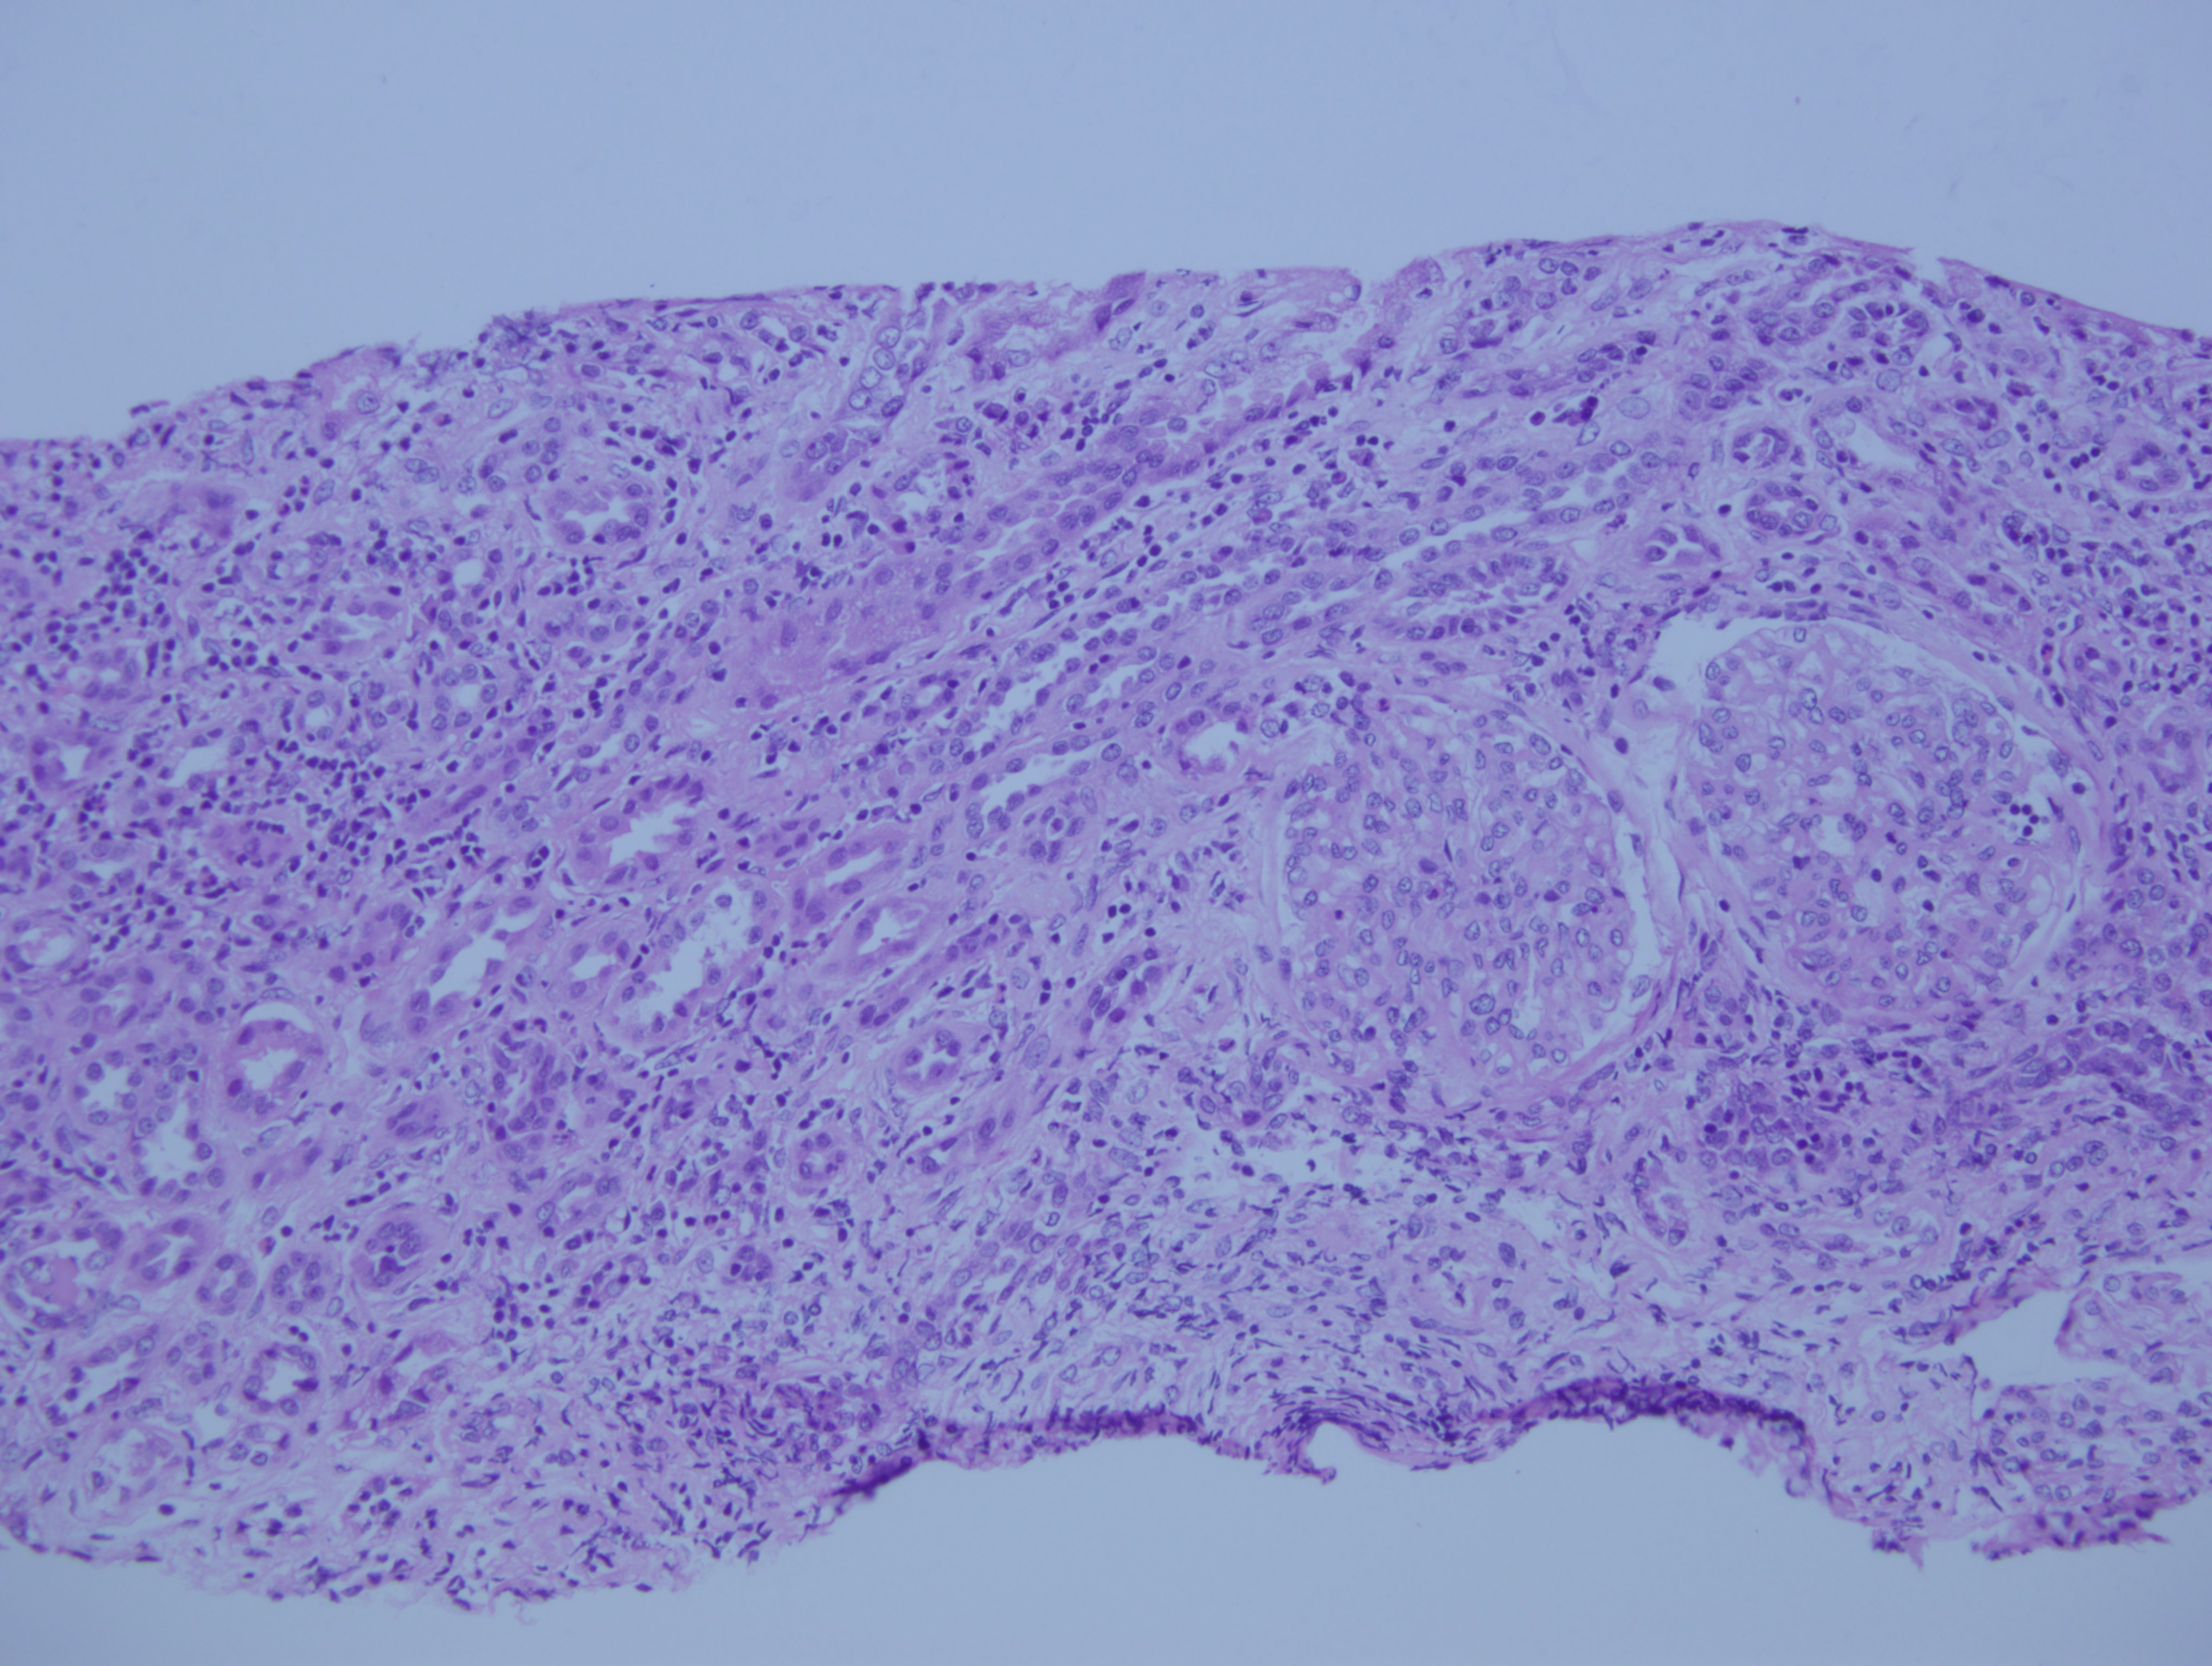

Biopsia renal, hematoxilina eosina

Nefritis tubulo intersticial por leflunomide